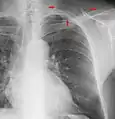

Chest X-ray PA inverted and enhanced.

Chest film showing increased opacity in both lungs, indicative of pneumonia